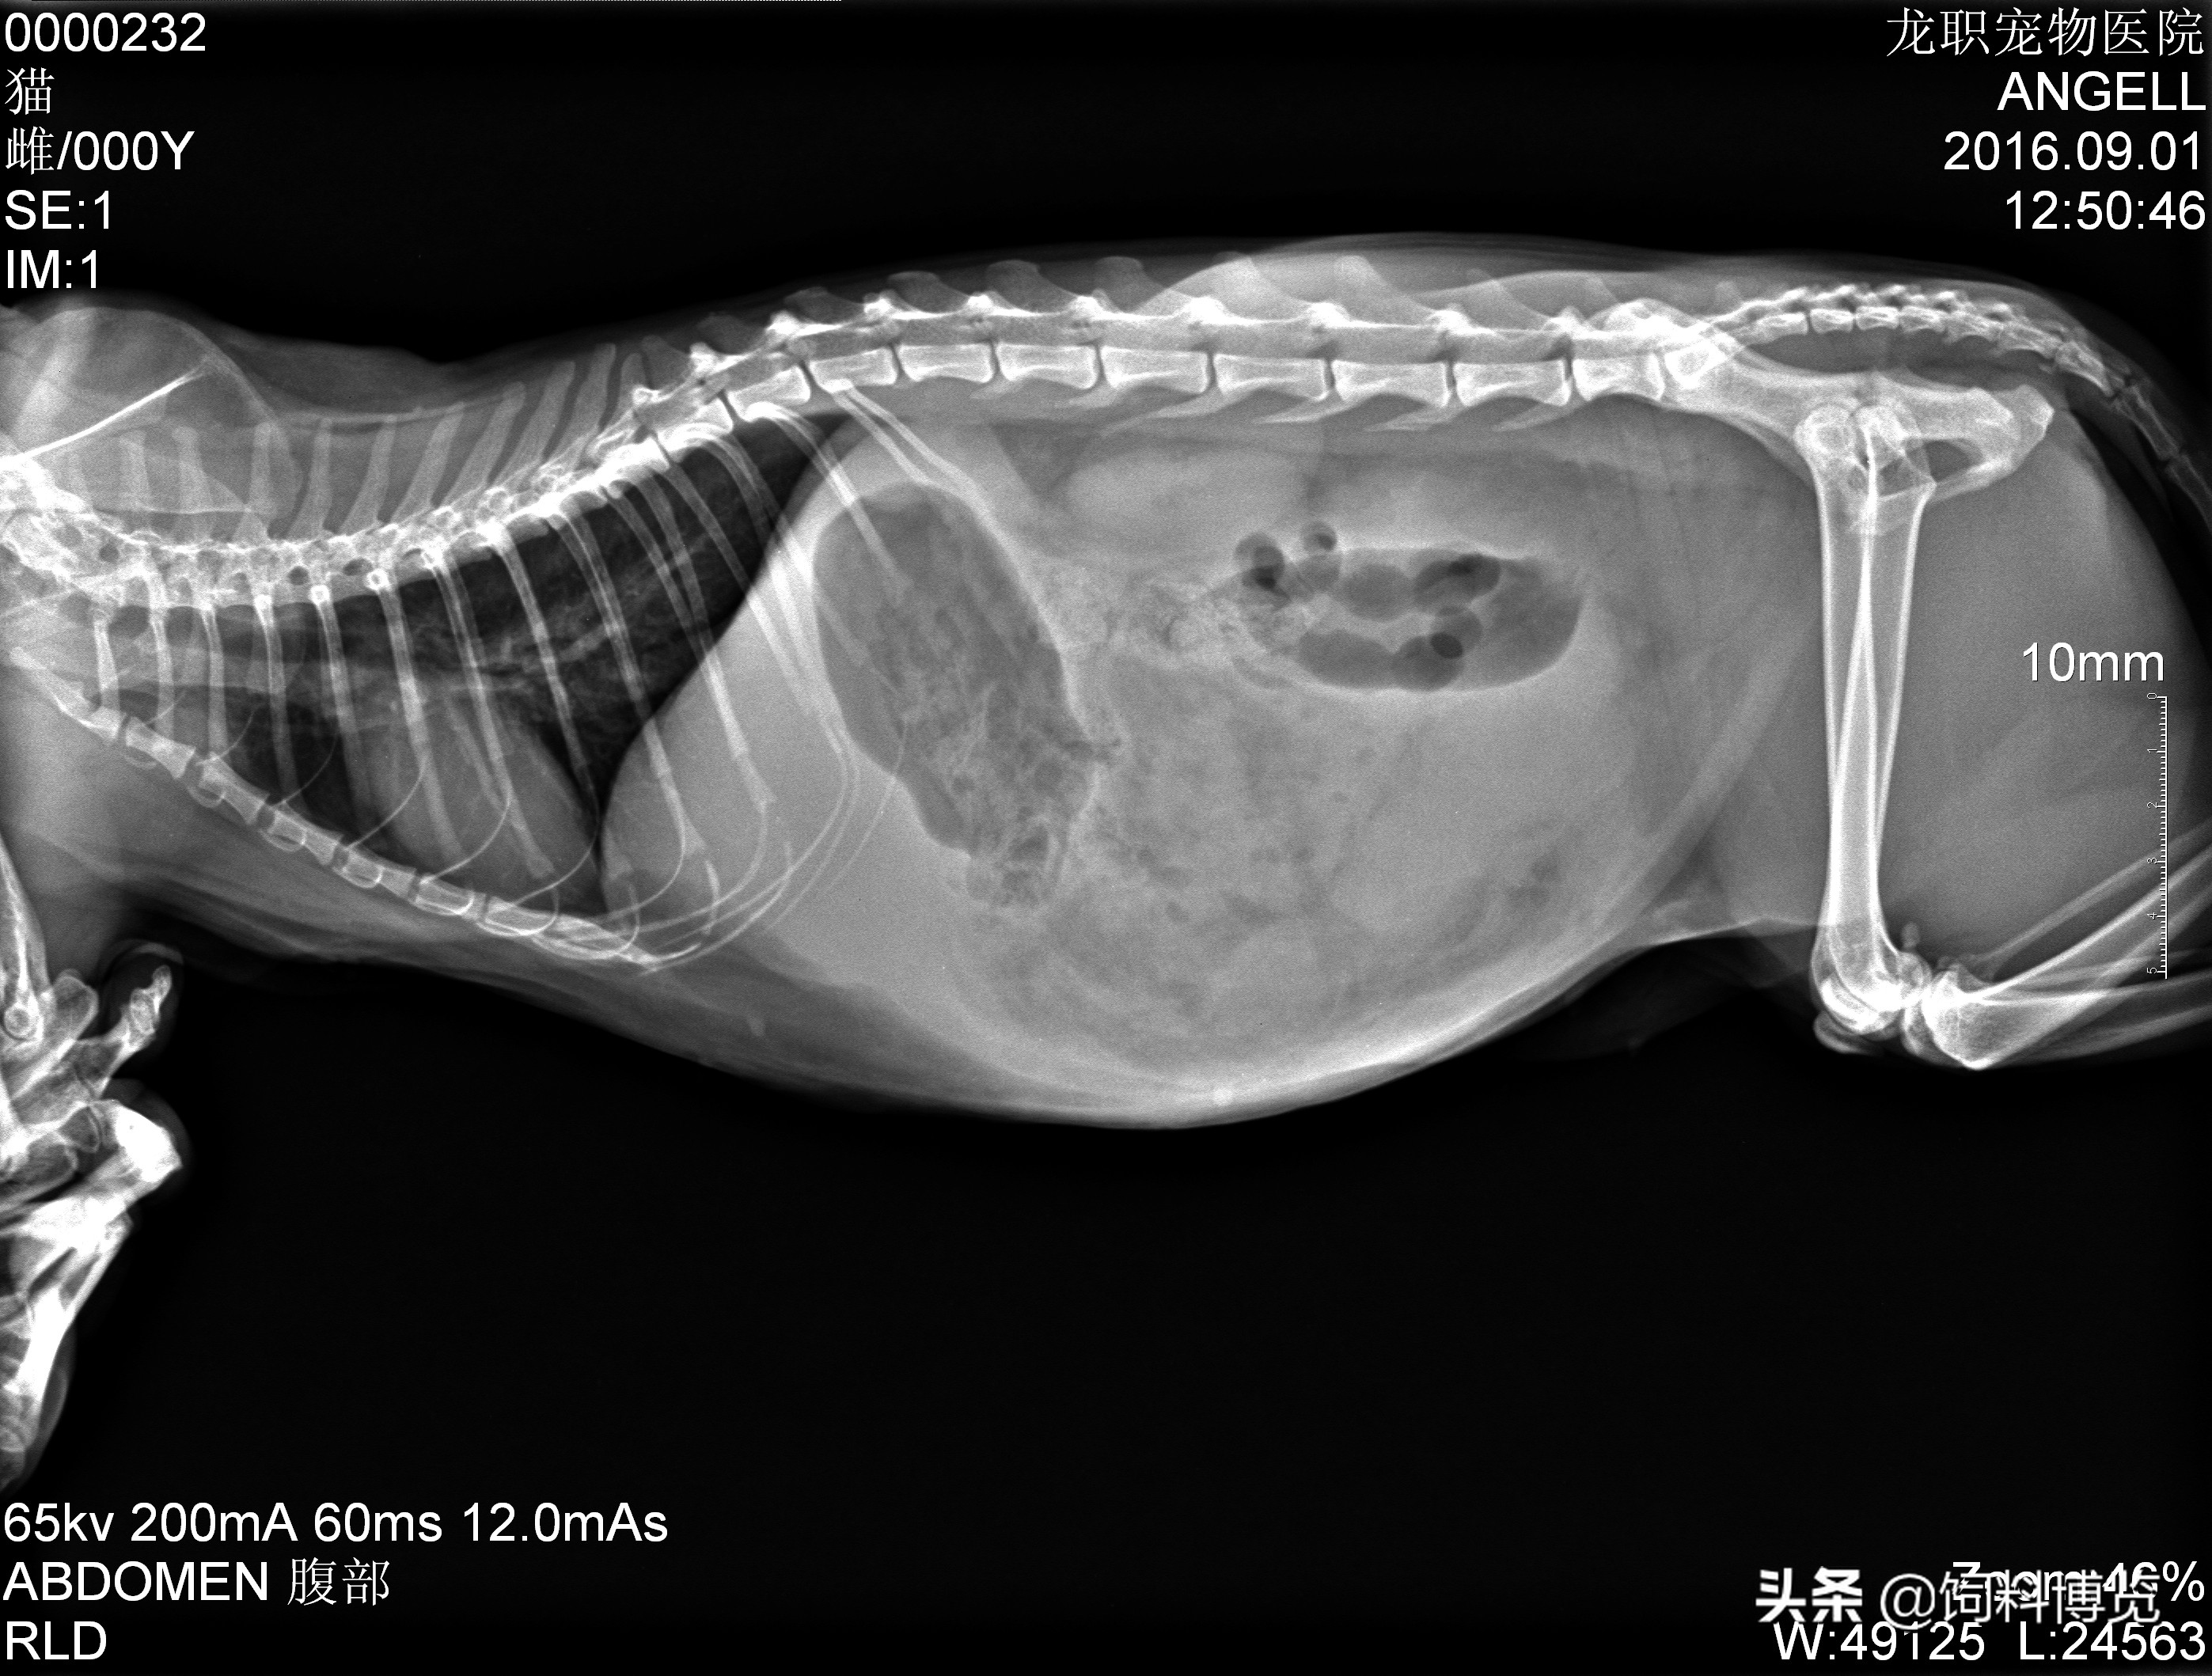

2.4 X线检查

X线检查发现腹腔模糊不清,右侧肾脏位置改变,脏器轮廓不清,如毛玻璃状。